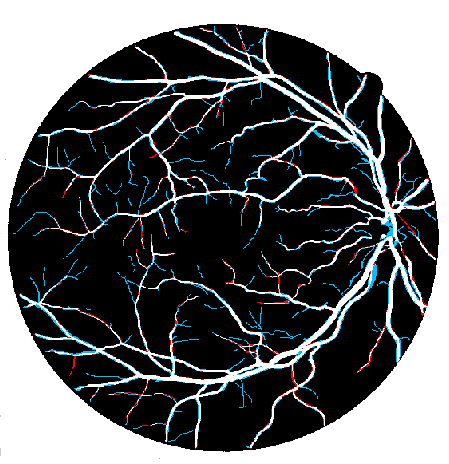

4.2 Validation of the Stationary Wavelet Transform

Having analyzed our Base System, we evaluate the effects of incorporating the SWT into it. The results of each variant are shown in Table 4, while the probabilistic predictions can be seen in Fig. 5. The patches coming from the SWT were concatenated in the input, by varying the total number of input channels. We resorted only to detail coefficients since the goal was to enhance image transitions. We started by concatenating the detail coefficients of the first level in the initial green channel input – BS + . Then, we added those of the second level – BS + + . Finally, only the latter were kept – BS + .

Analyzing the results of the tests performed, we notice that all the alternative strategies improved the performance of the Base System, in terms of Acc and AUC. This means that the use of features based on the wavelet decomposition, whose effectiveness for vessel segmentation is well-known (Soares et al.,, 2006; Zhang et al.,, 2017), is also beneficial when combined with a deep learning methodology. In particular, we see that the first level SWT coefficients used on BS + were less effective than those of the second level applied on BS + . The first level translates spectral information of higher frequencies; this seems to have induced more false positives, as can be seen in Fig. 5. On the other hand, the second level SWT coefficients introduced statistically significant differences to the Base System, in both Acc and AUC, which seems to reinforce the idea that even deep learning methods can benefit from domain knowledge. In fact, they allowed to reduce the combination of false positives and false negatives as we can see in Fig. 5 as well. From now on, we will refer to the best model (BS + ) as Proposed.